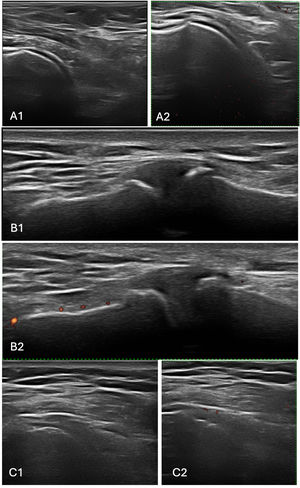

UltrasoundA musculoskeletal ultrasound (MSUS) examination of both shoulders was performed using the scanning technique proposed by the 2017 EULAR standardized procedures for ultrasound imaging in rheumatology.16 MSUS was performed with MyLab50® Xvision equipped with a 5/7.5/10MHz Mindray 7L4a linear probe, guided by an MSUS expert who was blinded to patients’ clinical and laboratory data at the time of the examination. Imaging was required to differentiate and verify RCT from disease activity. The anterior, lateral, and posterior aspects of the joint were scanned. Synovitis was defined according to the published definitions of Outcome Measures in Rheumatology (OMERACT).17 Cases of joint effusion, acromioclavicular synovitis, or glenohumeral synovitis were attributed to RA activity. Representative ultrasound images are shown in Figs. 2 and 3 illustrating findings in a patient with RA without RCT and another with RA+RCT, respectively

Ultrasound findings in a patient with rheumatoid arthritis without rotator cuff tendinopathy. Images of the left shoulder showing active synovitis and arthrosis of the acromioclavicular and glenohumeral joints. (A1) Longitudinal grayscale view of the anterior glenohumeral joint. (A2) Corresponding Doppler view. (B1) Grayscale image of the left acromioclavicular joint. (B2) Doppler image of the same region. (C1) Posterior glenohumeral joint in grayscale. (C2) Doppler image of posterior glenohumeral joint.